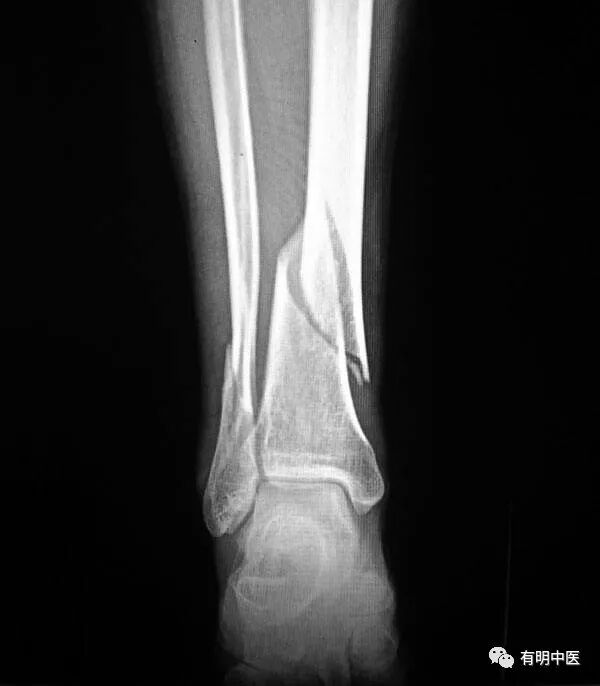

骨折后,一般局部淤血肿胀、疼痛,压痛明显,畸形,运动功能障碍。触诊,有骨擦音及高低不平的感觉。x线片可助诊断。

患者平坐在治疗床上,如有骨折伴错位时,一助手用双手稳定住患者的上身,一助手握住患肢足部呈对抗性牵拉,医生用双手握住伤肢,同时用拇指在突出点轻压复位(图82)。

螺旋形骨折伴错位时治疗,一般助手在向下牵拉的同时,将旋转畸形的伤肢,缓慢回旋至功能位,医生在助手牵拉,回旋的同时用握住骨折处的拇指在突起处下压复平,既对位。手法对位,以保胫骨为主,兼治腓骨。口服接骨续筋药。

对位后用夹板固定(图83)。随时观察体内的变化和扎缚的松紧。2周后,可改为三天复诊一次和增膝、踝关节的按摩。6周后可用一号外用洗药熏洗伤肢。8周后可以下床持拐功能锻炼,也是考虑去夹板的时期。